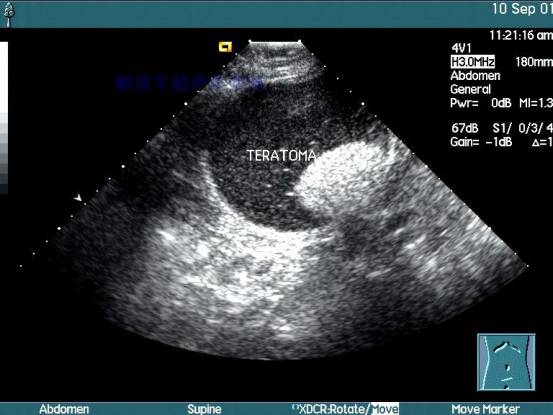

首先超声波检查是利用人体对超声波的反射进行观察。是子宫及其附件疾病和妊娠子宫判断的主要方法。

孕囊:增大的子宫轮廓中,宫腔内见到圆形或椭圆形的孕囊是超声首先观察到的妊娠标志,它是由绒毛膜形成的环形结构,也称妊娠环。孕囊在妊娠第4~5周时即可显示,直径为0.2~0.3cm。妊娠第7周孕囊占据宫腔的1/3, 直径为2.0cm,可以100%地被检出。妊娠第8周孕囊占据宫腔的1/2,第9周孕囊占据宫腔的2/3,第10周孕囊几乎占满整个宫腔。至妊娠12 ~ 13周,羊膜囊充满子宫腔。并与子宫壁重合,不再显示孕囊。

卵黄囊:妊娠第6周出现,10周的时候会渐渐消失,12周以前会全完消失。它的大小为3~5mm,是宫内妊娠的可靠标识。医生通过卵黄囊可以排除异位妊娠时在宫内的假性胚囊。当怀孕七周左右,如果在子宫里面没有看到卵黄囊,就以为这妊娠预后不良。所以这个卵黄囊可是妊娠早期的重要指示灯呢~

胎龄的估计:孕囊的大小以及其中胚芽的发育状态可作为妊娠发育和预后的重要指标(详情见《你知道胎龄怎么估算吗?》),对月经不规则或末次月经难以确定的女性,测量孕囊大小就可以估算出妊娠时间,以及评估胎宝宝在子宫内发育的状况了。

首先诊断是否妊娠,阴道超声可在停经30天左右发现孕囊 (相当于排卵后16天或着床后10天),腹部超声可在停经 35天(排卵后21天)诊断早孕;